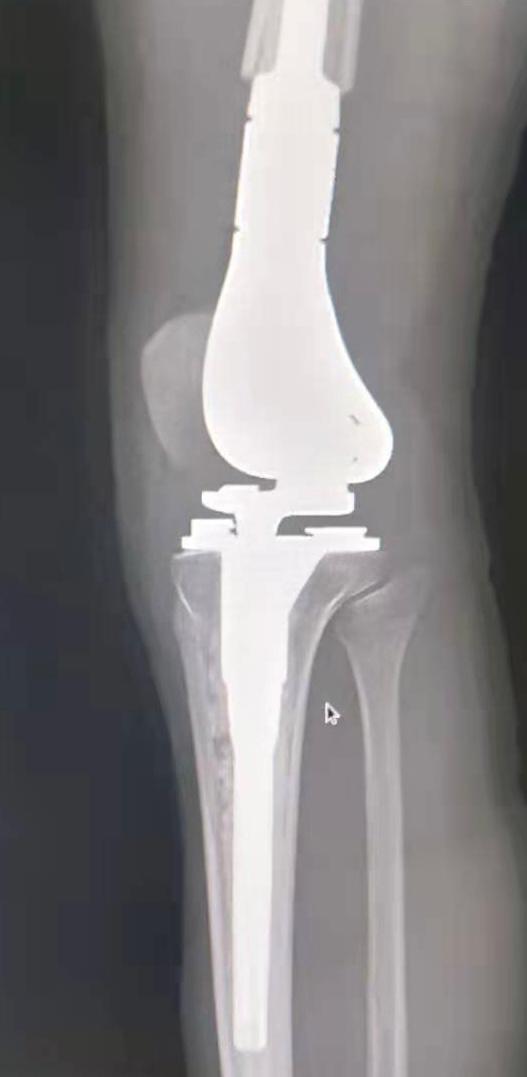

2.发病部位主要集中在关节周围,大约2/3的在股骨远端,胫骨近端第2位,肱骨近端第3位,约占10%。